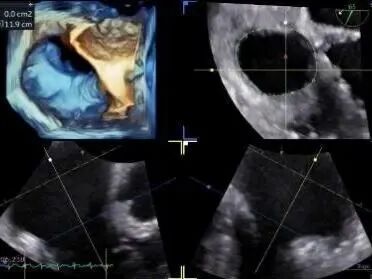

During the procedure, close collaboration was maintained with Dr. Yang Yan (anesthesiologist, Department of Anesthesiology) and Dr. Niu Ming (echocardiography specialist, team of Director Zhai Hong, Department of Cardiac Ultrasound). Guided by transesophageal echocardiography and assisted by DSA imaging, the tricuspid annular structure and regurgitation jet direction were precisely assessed. Ultimately, two 12T K-Clip® devices were successfully implanted. Immediate postoperative echocardiographic evaluation showed a significant reduction in tricuspid regurgitation from 4+ preoperatively to 1+, with a marked decrease in annular area. The surgical outcome was satisfactory.

Echocardiographic: Severe tricuspid regurgitation (grade 4+), with the regurgitant jet mainly located at the posteroseptal and central regions. No significant dilatation of the tricuspid annulus is observed. Mild myxomatous degeneration of the tricuspid leaflets is present, showing Barlow-like morphology, with leaflet prolapse of 3.7 mm in height.

Preoperative Regurgitation: 4+

Annulus Area: 11.3 cm²

Postoperative Regurgitation: 1+

Annulus Area: 4.9 cm²